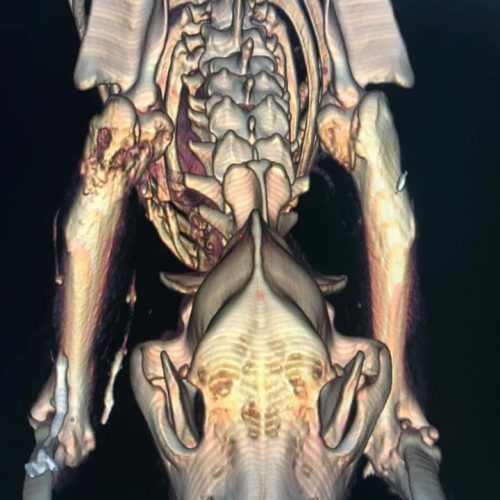

TC MULTISTRATO